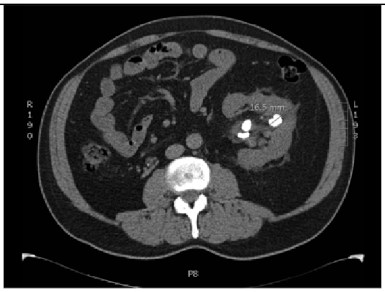

2.6.1. Test Procedure

The stress test involved simulating varying numbers of concurrent users querying the system. For each LLM, we executed 20 clinically relevant prompts, as shown in (Table A2) in the Appendix A. For each VLM, 10 different images with 2 prompts per image resulting in a total of 20 prompts per model were tested. The specific prompts used are listed in (Table A3) in the Appendix A. We tested user loads of 10, 20, 30, 40, 50, 75, 100, 125, and 150 users. In order to measure the robustness of the container as well as the robustness of JAVIS, this experiment queried the JAVIS back-end to measure the complete roundtrip response times. This approach ensured that the test accurately reflected real-world usage scenarios, including the overhead of back-end processing and model orchestration.

JAVIS supports multimodal LLMs or VLMs, allowing the integration of various image types (JPG, PNG, etc.). This enhancement significantly increases the system’s versatility in handling diverse clinical inputs, enabling more comprehensive and accurate patient interactions.